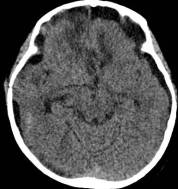

病例1:患儿男性,9岁。因反复出现意识丧失、视力下降半年收入院。入院后CT及 MRI显示颅内有形态不规则、“超大型”的颅咽管瘤,最大径约10厘米,见图1、图2。

图1.术前CT显示典型的囊性颅咽管瘤